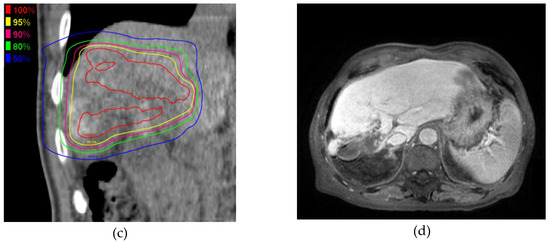

Figure 2 shows the MRI and PBT planning results of a successfully treated 64-year-old man with a large HCC in the right hepatic lobe (Figure 2a). He was treated with PBT at 80 GCE in 25 fractions (Figure 2b,c). The tumor shrank and was controlled 2 years after PBT (Figure 2d). He showed no severe complications during a 2-year follow-up.

Figure 2.

A 6.3 cm hepatocellular carcinoma (HCC) was treated by proton beam therapy (PBT) in a patient with Child–Pugh class A liver disease and right portal vein tumor thrombosis. (a) Early enhancement of the HCC was shown in the arterial phase of gadolinium ethoxybenzyl diethylenetriamine pentaacetic acid-enhanced dynamic magnetic resonance imaging (Gd-EOB-MRI); (b) The isodose lines were shown on planning CT (axial view); (c) This tumor was close to the colon (coronal view); (d) HCC was shown in the arterial phase of EOB-MRI 2 years after PBT.